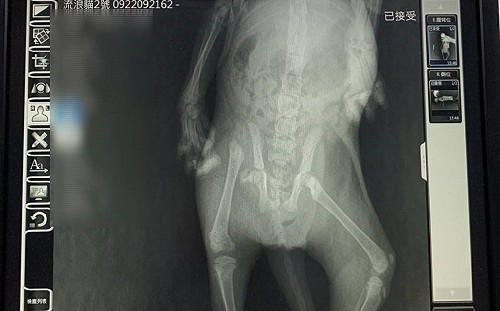

斷骨小黑貓石縫中求生 新北3獸醫聯手2小時妙手回春